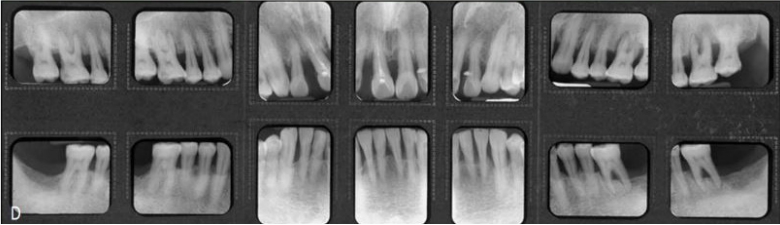

[증례] 치주질환으로 심한 병적 치아이동(pathologic tooth migration, PTM)이 나타나 기능적, 심미적 회복을 위해 교정을 한 65세 고령 환자 증례. 전악 치근단사진에서 볼 수 있듯이 전치 뿐 아니라 구치부 전 치아에 걸쳐 심한 염증이 발생하고 이로 인해 구치부에서도 PTM 이 심하게 나타나 치주치료 후 구치 교합이 불안한 상태가 초래 된 환자이었다.

치주치료 후 보철의사에게 돌아온 환자의 교합을 보고 dual bite 상태에서는 보철을 할 수 없는 바, 치주질환 이전의 교합 상태로의 교정을 의뢰하였다. 전체적으로 치주지지가 불량하여 움직일 치아만 제대로 움직 이는 치료가 매우 어려운 케이스이기 때문에 기공비용이 다소 많이 들지만 간단하게 치료 할 수 있는 투명교정장치를 사용하여 치료하기로 하였다. 구치부의 경우 협측전위된 우측 제1, 제2소구치와 좌측 제1소 구치 이동을 위해 투명교정장치를 사용할 경우 다수의 장치가 필요할 것으로 생각되어 대구치를 고정원으로 하여 소구치를 간단 하게 이동시키는 TPA 장치를 이용하였으며, 이후 투명교정장치로 전치부 공간을 클로져하여 간단하게 교정을 마무리 하였다(그 림 23-5, 6).